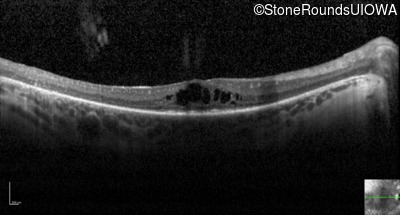

Optical Coherence Tomography - Right - 20/60 -1

Exemplar / OCT Stack